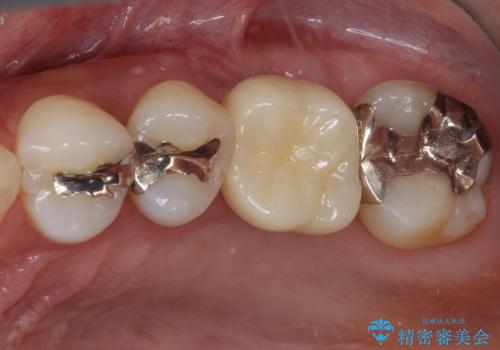

- 転倒により前歯3本が折れてしまったとのことで、インプラントによる治療を希望して来院された患者様です。

既に近医で真ん中の歯1本は抜歯されており、その隣の2本も破折していると言われたとのことでした。

診断をした結果、前医の診断の通り、2本とも破折しており、既に抜去している歯を含めて3本の抜歯が必要な状態でした。

抜歯する歯の両隣も治療が必要と思える歯であったため、広範囲なオールセラミックブリッジによる治療も提案しましたが、患者様本人の希望もあってインプラント2本による欠損部のみのブリッジ治療を行うこととしました。

治療により前歯は非常に安定しましたが、インプラント部の両隣、特に反対側の前歯はクラウンのやり直しが必要な状態であったので、今後反対側の治療も実施していく予定です。